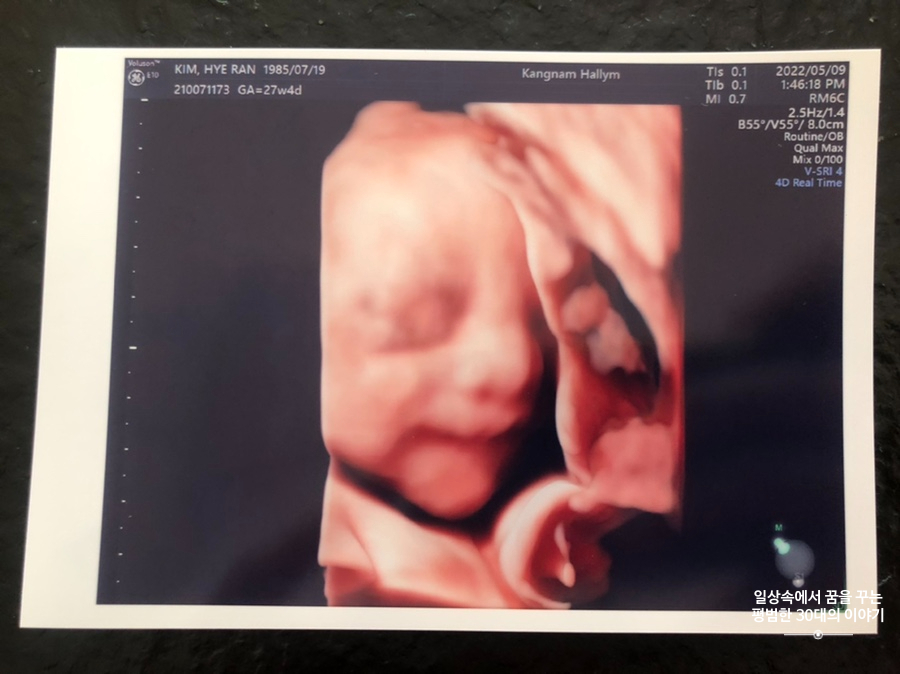

오늘은 입체 초음파 보는 날!!! 입체 초음파는 처음인데다 3주 만에 이안이 얼굴을 본다 생각하니 무척 설레는 마음으로 병원에 갔다. 첫 번째 시도에서는 계속 내 등 쪽으로 얼굴을 대고 엎드려 있어 실패! 초코우유 먹고 열심히 걸은 후, 30분 뒤에 다시 진행한 두 번째 시도에서는 얼굴 반쪽을 보여줬다. 얼굴 전면을 보지 못해 너무 아쉬웠지만 그래도 손가락 빨고 있는 모습, 웃고 있는 모습, 입 뻐끔 거리는 모습, 발차기 하는 모습, 손가락 쥐었다 폈다 하는 모습, 손을 휘적휘적 거리는 모습 등 다양한 모습을 보여줘서 그것만으로도 충분히 만족스러웠다. 내가 다니고 있는 강남성심병원은 입체 초음파가 다른 병원에 비해 무척 비싼 편인데(진료비 내역을 보니 초음파 진단료가 129800원 나옴) 그나마 위안을 삼을 수 있는 것은 화질이 그나마 좋은 편이라는 것이다.